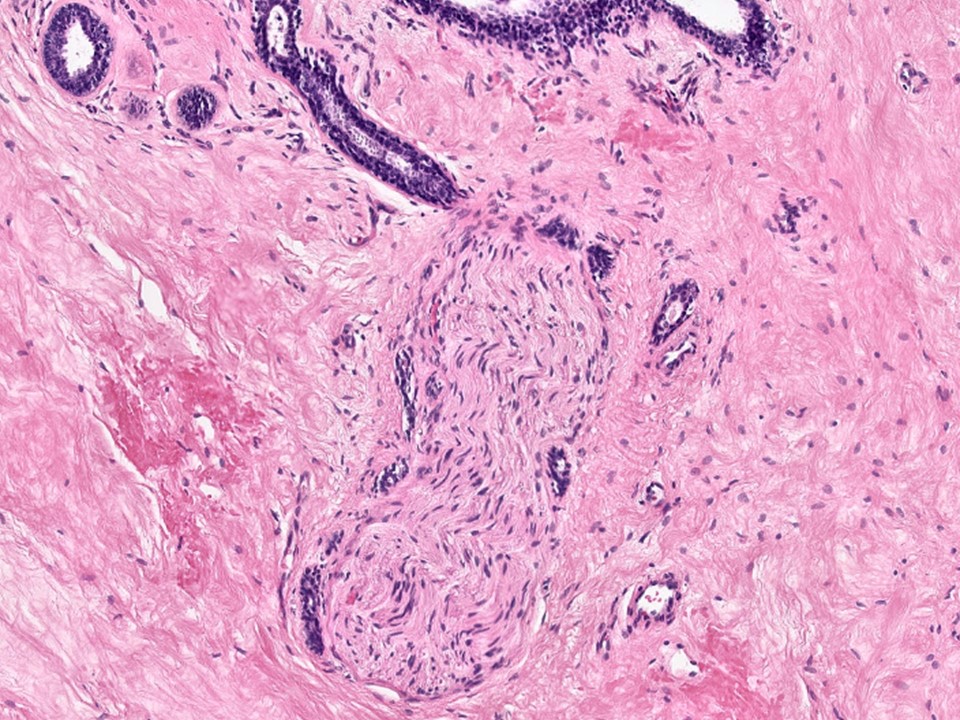

Adenosis with Perineural Involvement

Sclerosing adenosis sometimes infiltrates nerves, although uncommonly, and should not be taken as an indication of malignancy. As seen here, benign glands can be seen adjacent to nerve twigs.

For reference: https://www.ncbi.nlm.nih.gov/pubmed/6073901